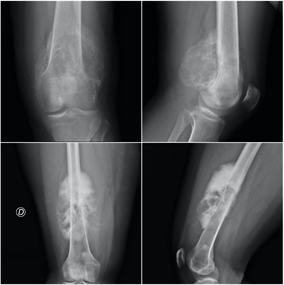

Siempre debemos estar atentos a los síntomas que nos refieren los pacientes, el tiempo de evolución y la respuesta a los tratamientos realizados. En los estudios de radiografías debemos igualmente observar con detenimiento cualquier alteración del hueso que se diferencie de los patrones radiológicos normales, con fin de detectar las anomalías óseas e iniciar el estudio y los tratamientos de una forma precoz y adecuada, muchas veces junto a un equipo multidisciplinar. En las radiografías debemos prestar atención a la localización de la lesión, su forma, tamaño, matriz ósea, la existencia de reacción perióstica o afectación de partes blandas.

El quiste óseo aneurismático, aunque es un tumor benigno, es localmente agresivo. Constituye alrededor del 2% de los tumores benignos del hueso en menores de 20 años. En las radiografías se suele observar una lesión lítica y expansiva con elevación del periostio y en ocasiones márgenes mal definidos que recuerdan a una lesión maligna, por lo que podría precisar biopsia y análisis anatomopatológico en algunos casos. La fractura patológica se produce hasta en el 30% de los casos, precisando estabilización quirúrgica en caso de fracturas desplazadas y tratamiento específico con aporte de injerto óseo para su tratamiento definitivo.

El tumor de células gigantes es una lesión tumoral benigna pero localmente agresiva. Provoca lesiones líticas expansivas que se localizan fundamentalmente en las metáfisis y epífisis de huesos largos. La edad de aparición está entre los 20 y 50 años y se suele localizar con mayor frecuencia en la zona cercana a la rodilla, en la epífisis distal del fémur, en la tibia proximal y en el radio distal. Se describe la presencia de metástasis pulmonares en casi el 5% de los pacientes. Habitualmente el paciente refiere una historia de dolor persistente en torno a la rodilla, con afectación progresiva de la funcionalidad. Las fracturas patológicas suelen aparecer fundamentalmente en casos avanzados, con gran debilidad cortical. En la rodilla puede asociar derrame articular y fracturas osteocondrales por debilidad del hueso subcondral.